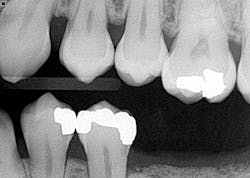

- Additional caries were noted on nos. 10, 11, 14, 26, 27, and 29—primarily facial/buccal caries (figures 3–8)

- In the aforementioned treatment plans, nowhere was it noted or discussed what would happen to the caries on the other teeth aside from nos. 8, 9, and 22.